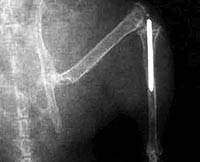

Un joven austríaco lleva prótesis en los brazos dirigidas por su cerebro

Es el primer europeo, y la tercera persona en el mundo, que se beneficia de este invento que le permitirá volver a trabajar